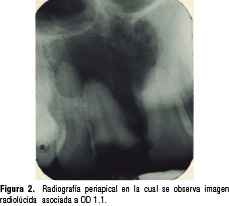

Se toma radiografía periapical, observando una imagen radiolúcida asociada a raíz de órgano dental (OD) 1.1, de 2.5 cm aproximadamente, unilocular, no corticalizado, bordes poco definidos, que se extiende hacia el piso nasal y hacia OD 1.2 a 2.1 (Figura 2).

diego2.jpg